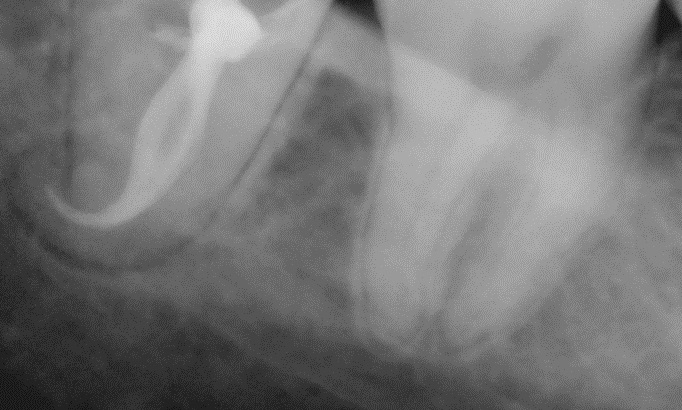

paraschyk1 Опубликовано 13 августа, 2014 Автор Опубликовано 13 августа, 2014 Самый сложный пульпитец па последние полугодие. Три часа работы.